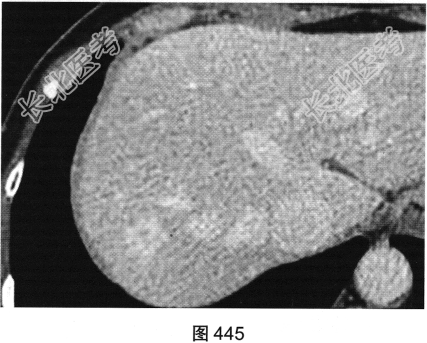

患者女性,53岁,体检经上腹部超声发现肝右叶一个稍高回声光团。查体:腹平软,右上腹无压痛,无反跳痛,肝脾肋下未及,Murphy征阴性,肝浊音界存在,肝上界位于右锁骨中线第五肋间,肝区无叩击痛,移动性浊音阴性。实验室检查:肝功能未见异常,AFP(—)。患者进一步行上腹部CT检查,如图442~图445所示。

- 多项选择题1.请问CT图像中可见哪些影像学发现( )

D、增强扫描动脉期病灶边缘结节状强化,强化程度与血管接近

F、增强扫描门脉期及延迟期强化范围向病变中心逐渐扩展

- 多项选择题2.结合患者临床及影像资料,病变最可能的诊断是( )

E、肝海绵状血管瘤